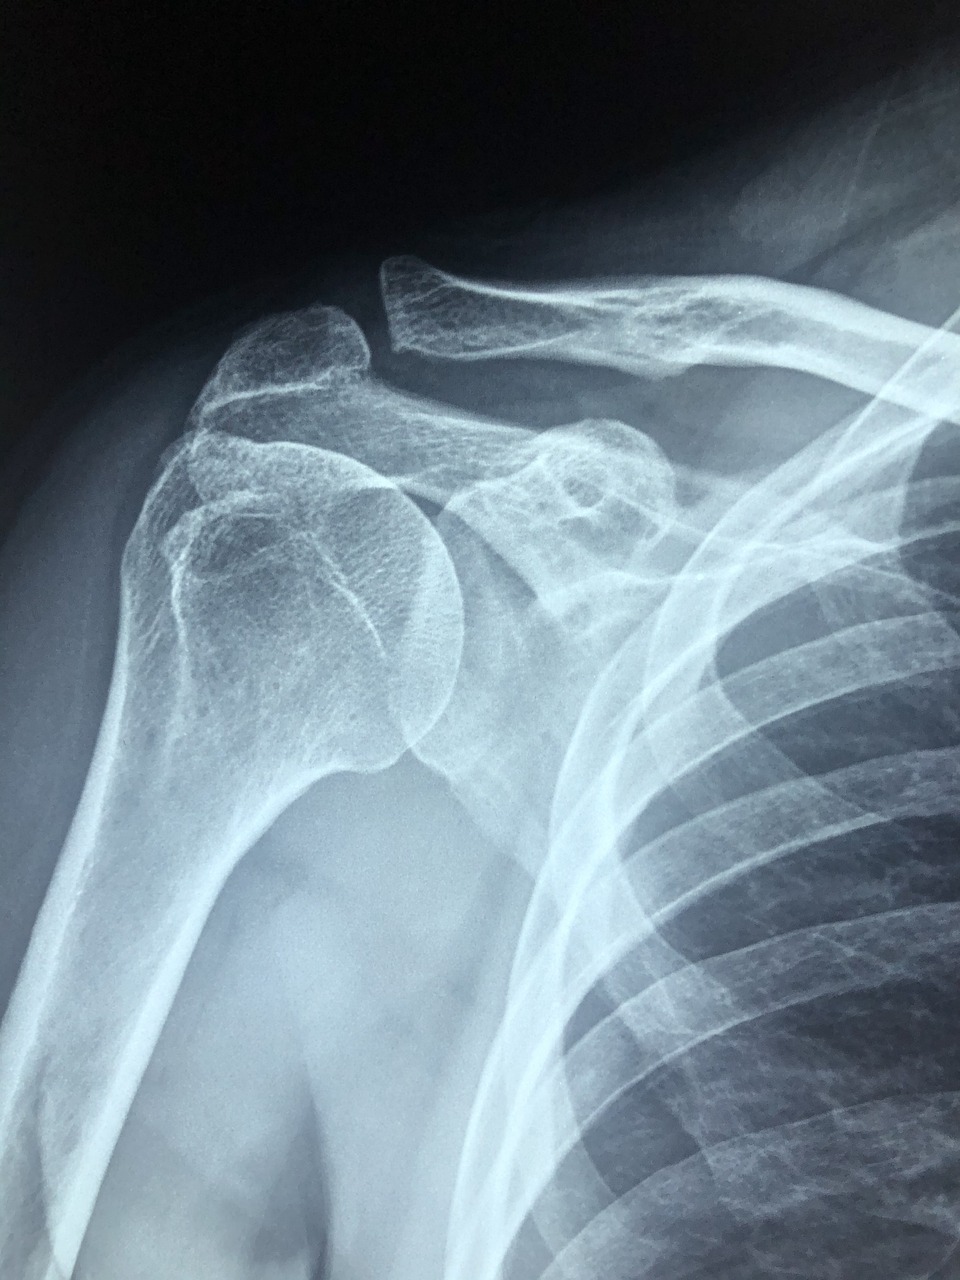

● 스테로이드 주사는 어깨 관절에 생긴 염증을 빠르게 가라앉히기 위해 사용하는 항염증 치료법입니다. 특히 회전근개염, 오십견, 석회성건염 등에서 급성 통증 완화에 많이 사용됩니다.

● 일반적으로 병원에서는 초음파 유도 하에 어깨 관절 내부에 직접 주사액을 주입합니다. 효과는 2~3일 내에 나타나며, 통증이 눈에 띄게 줄어드는 경우가 많습니다.

● 스테로이드 성분은 강력한 항염효과가 있는 만큼, 지나치게 자주 사용하면 힘줄(건) 약화와 연골 손상이 일어날 수 있어요. 특히 회전근개 파열 위험이 높아질 수 있으며, 이는 이후 수술로 이어질 가능성도 있습니다.